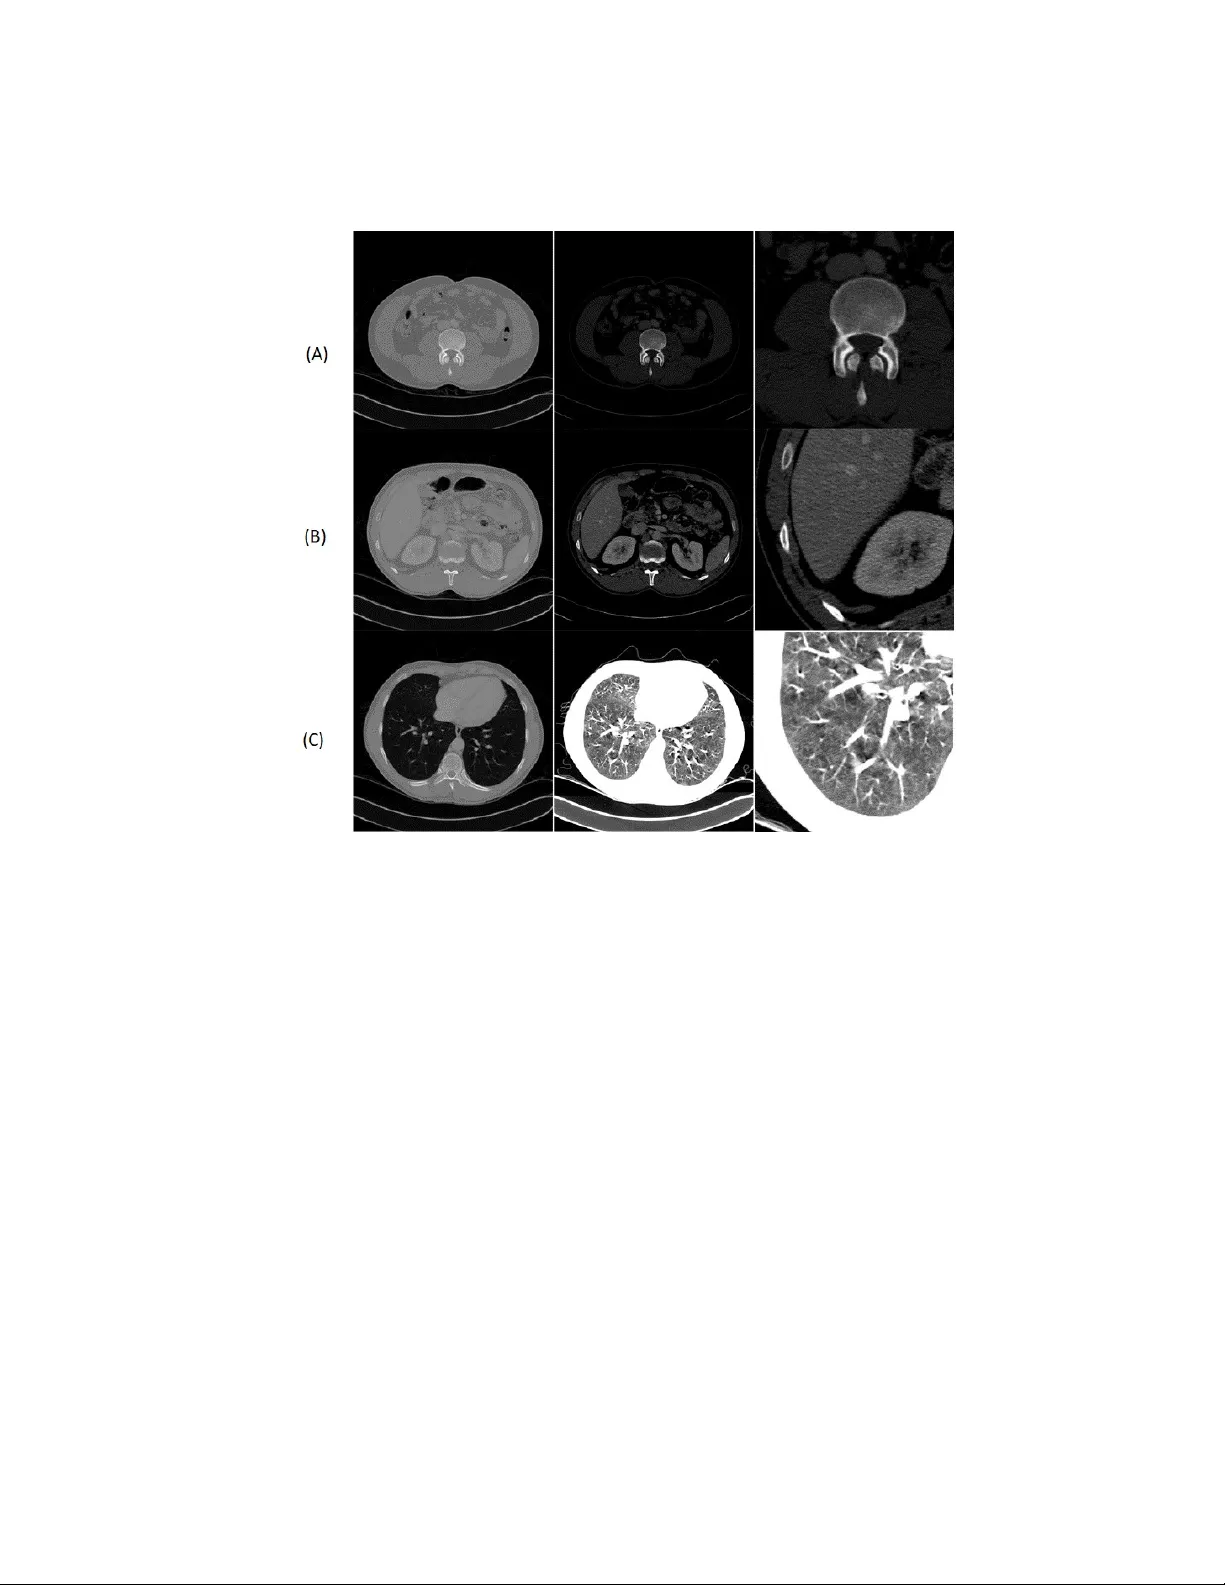

Domain sp ecific cues impro v e robustness of deep learning based segmen tation of ct v olumes Marie Klo enne 1 , 2 ? , Sebastian Niehaus 1 , 3 ? , Leonie Lamp e 1 , Alb erto Merola 1 , Janis Reinelt 1 , Ingo Ro eder 3 , 4 , and Nico Sc herf 4 , 5 1 AICURA medical, Bessemerstrasse 22, 12103 Berlin, Germany firstname.lastname@aicura-medical.com 2 T ec hnische F akult¨ at, Univ ersit¨ at Bielefeld, Universit¨ atsstrasse 25, 33615 Bielefeld, German y 3 Institute for Medical Informatics and Biometry , Carl Gustav Carus F acult y of Medicine, T ec hnische Univ ersit¨ at Dresden, F etscherstrasse 74, 01307 Dresden, German y 4 National Cen ter of T umor Diseases (NCT), Partner Site Dresden, 01307 Dresden, German y 5 Max Planc k Institute for Human Cognitive and Brain Sciences, Stephanstrasse 1a, 04103 Leipzig, German y Abstract. Mac hine Learning has considerably impro ved medical image analysis in the past y ears. Although data-driven approaches are intrin- sically adaptive and thus, generic, they often do not p erform the same w ay on data from different imaging modalities. In particular Computed tomograph y (CT) data p oses man y challenges to medical image seg- men tation based on con volutional neural netw orks (CNNs), mostly due to the broad dynamic range of in tensities and the v arying num b er of recorded slices of CT volumes. In this pap er, we address these issues with a framew ork that com bines domain-specific data prepro cessing and augmen tation with state-of-the-art CNN architectures. The focus is not limited to optimise the score, but also to stabilise the prediction p erfor- mance since this is a mandatory requirement for use in automated and semi-automated w orkflows in the clinical en vironment. The framew ork is v alidated with an architecture comparison to show CNN arc hitecture-indep enden t effects of our framew ork functionalit y . W e compare a modified U-Net and a mo dified Mixed-Scale Dense Netw ork (MS-D Net) to compare dilated conv olutions for parallel multi-scale pro- cessing to the U-Net approach based on traditional scaling operations. Finally , we prop ose an ensemble mo del combining the strengths of dif- feren t individual metho ds. The framew ork performs w ell on a range of tasks suc h as liver and kidney segmen tation, without significant differences in prediction p erformance on strongly differing volume sizes and v arying slice thickness. Thus our framew ork is an essen tial step tow ards p erforming robust segmentation of unkno wn real-world samples. ? The authors con tributed equally to this pap er. In tro duction Spatial c haracteristics of tumours lik e size, shape, lo cation or gro wth pattern are cen tral clinical features. Changes in these characteristics are essential indicators of disease progression and treatmen t effects. Automated, quan titative assessment of these c haracteristics and their c hanges from radiological images w ould yield an efficien t and ob jectiv e to ol for radiologists to monitor the course of the disease. Th us, a reliable and accurate automated segmentation metho d is desirable to extract spatial tumour and organ characteristics from computed tomography (CT) v olumes. In recent years, conv olutional neural netw orks (CNNs) (Krizhevsky , Sutsk ev er, & Hin ton, 2012) b ecame the state of the art method for image segmen tation, as well as many other tasks in computer vision (V oulodimos, Doulamis, Doulamis, & Protopapadakis, 2018), suc h as image classification, ob ject detection and ob ject trac king (Mo en et al., 2019). The applications of CNNs are div erse, but the general data handling or prepro cessing is often very similar in each case since the feature extraction is p erformed internally by the CNN itself. Improv emen ts in the application of CNNs for medical image processing often address the neural net work arc hitecture, the training algorithm or the use case (Minnemaa et al., 2018; Chlebus, Schenk, Moltz, v an Ginneken, & Hahn, 2018). At the same time, most authors tend to ignore the data handling itself, treating medical images suc h as CT volumes the same wa y as grayscale images or RGB images just with additional dimensions. Ho wev er, this approac h neglects prior information about the sp ecific ph ys- ical pro cesses that underlie images acquisition and determine image contrast, p ossibly leading to sub optimal and sometimes inaccurate image analysis. F or instance, while most image formats map pixels on relative scales of a few hun- dred v alues, vo xels in CT volumes are mapp ed on the Hounsfield scale (Bro der, 2011), a quantitativ e mapping of radio density calibrated such that the v alue for air is -1000 Hounsfield Units (HU) and that for w ater is 0 HU, with v alues in the h uman b ody reaching up to ab out 2000 HU (cortical bone). Therefore, in con trast to most standard images where pixel intensities themselves migh t not b e meaningful, the actual grey v alues of CT volumes carry tissue-sp ecific information (Brenner, 2007), and sp ecial consideration is required to leverage it. The tissue-specific information also means, that CT data t ypically contains a range of v alues that are not necessarily relev an t for a particular diagnostic ques- tion (Costello e e t al., 2013; Harris, Adams, Lloyd, & Harvey , 1993). Thus, when radiologists insp ect CT volumes for diagnosis, they typically rely on windowing, i.e. they restrict the range of display ed grey v alues to fo cus the image infor- mation to relev ant v alues. CNN-based image segmentation framew orks rarely include suc h p oten tially essential steps from the exp ert workflo w. They are as- suming that the data only has to b e normalised and the net work will then learn b y itself to fo cus on the relev ant image regions. In this paper, we address the c hallenges of a clinically meaningful CT vol- ume pro cessing and present a domain specific framew ork for CNN based image segmen tation. The prop osed framework is inspired b y insights on b oth the data acquisition pro cess and the diagnostic pro cess p erformed b y the radiologist, ad- dressing in particular the spatial information CT volumes and the use of the HU scale. Our fo cus is not on the optimisation of the loss function on the whole dataset, but instead on obtaining a robust segmen tation quality , indep enden t of the dif- ferences in size and shap e of the input volumes. F or this reason, we also consider the standard deviation of the dice score as a measure of robustness for ev aluation. If we use a segmentation mo del in an automated or semi-automated pro cess in whic h the result of the segmentation is not directly analysed, particularly strong segmen tation errors p ose a problem b ecause the user tends to rely on the seg- men tation mo del and only analyse the final result of the pro cess. Therefore, our goal is to specifically address the demands of algorithms for CT pro cessing in the clinical environmen t, where w e require algorithms to pro cess eac h volume consisten tly and without significant differences in the quality of the output. W e ev aluated the framework with a mixed-scale dense conv olutional neural net work (MS-D Net) (Pelt & Sethian, 2017) with dilated con volutions and the nnU-Net (Isensee et al., 2018) with traditional scaling op erations, which is a mo dified U-Net (Cicek, Abdulk adir, Lienk amp, Brox, & Ronneberger, 2015). W e consider b oth a 2D-CNN and a 3D-CNN implementation for each architecture. Finally , w e sho w an ensemble CNN, which allows combining the longitudinal information leveraged in 3D-CNNs with the prop ortionally higher v alue of each segmen ted v oxel in the 2D-CNNs training pro cess, resulting in more accurate results from a theoretical p oin t of view. The t ypical assumption b ehind cross- v alidation is that the data set is represen tative of y et to b e seen real data, and the test or v alidation sample should also reflect this. Th us, w e would usually balance all folds, so they contain typical samples and also p ossible outliers. But we wan t to assess how robust the trained mo dels are and thus we do not randomly mix the folds. Instead, we assign each sample to a fold dep ending on the num b er and thickness of its slices. This w ay , we will alw ays ha ve samples in the test set that are indep enden t of the training data, and w e simulate the w orst-case scenario for the application in the clinical environmen t. In order to make the results repro ducible, we use op en datasets for training and ev aluation. W e train and v alidate the CNN-mo dels for kidney tumour segmen tation on the dataset of the 2019 Kidney T umor Segmentation Challenge (Heller et al., 2019). F or the liver segmentation, we use the dataset of the CHAOS - Com bined (CT-MR) Health y Ab dominal Organ Segmen tation Challenge (Selver et al., 2019). It seems lik e the rise of Deep Learning metho ds in medical image analysis has split the comm unity in to tw o factions: those who em brace such methods and those who do not trust them. W e think that to apply Deep Learning in a clin- ical setting, the CNN architectures and the entire workflo w for data pro cessing and augmentation need to b e adapted, requiring considerable knowledge of the diagnostic question and the imaging mo dalit y at hand. In this work, we w ant to sho w that in order to build clinically applicable CNN-based frameworks, we require differen t exp ertise and input from tec hnical and medical domain experts. Metho d In the follo wing, w e describe the data preprocessing and augmen tation in section 1, the netw ork architectures in section 1 and the training pro cedure in section 1. The prepro cessing includes volume shape reduction and grey-v alue windowing. The prop osed augmentation addresses the scarcity of data, with the aim of pro- viding additional samples for the training pro cedure. F or the CNN architectures w e consider tw o mo dels: one with dilated conv olutions (MS-D) and one with traditional scaling op erations (U-Net). W e further explain the construction of the stac ked CNN mo del. Subsequently , in section 1 the training pro cedure for the t wo considered architectures is describ ed. Prepro cessing and Augmen tation In order to ensure an adequate data qualit y in the training pro cess for each mo del, we adapt the data prepro cessing and augmentation for CT data. The follo wing description of prepro cessing is tailored to the dataset of the KiTS Kidney T umor Segmentation Challenge (Heller et al., 2019) and the dataset of the CHA OS - Combined (CT-MR) Healthy Ab dominal Organ Segmen tation Challenge (Selver et al., 2019), but can b e applied to any other CT dataset with minor c hanges. Image Prepro cessing The image normalization is adapted from (Isensee et al., 2018) and further extended to make it more general and enable a more realistic normalization for real life applications. W e adapted the image normalisation from (Isensee et al., 2018) to b etter suit real-w orld applications. T o reduce the complexit y and optimise the dynamic range, we apply a windo wing to each v olume by clipping the vo xels grey v alue range to a (0.6, 0.99) p ercen tile range that corresp onds to the window a ra- diologist would use for decision-making. F or other segmentation problems, the p ercen tiles m ust b e adjusted to fit the in tensity distribution of the relev ant bo dy parts (W e show examples in Figure 1 ). W e then normalise the window ed data using the z-score using the intensit y statistics (mean, standard deviation) from only a random sample of the data set. Using the statistical information from the full dataset w ould b e b etter but do es not reflect the real conditions in a clinical en vironment. In order to sav e costs and time and reduce exposure to radiation in CT acquisition, the radiologist typically confines a CT acquisition to the region of in terest (ROI) ( Figure 2 ). This ROI typically defined lib erally not to miss an area that is p otentially relev an t to the diagnosis. Th us, in a clinical setting, the num ber of acquired slices in a CT volume considerably v aries. This p oses a challenge to the application of standard CNN pip elines which often assume a regular data sampling. T o standardise the data, we decided to reduce each v olume to 16 slices as we do not need to upsample volumes that con tain only a few slices. Instead, our metho d selects slices at random from eac h volume, and Fig. 1. Three examples for the use case orien ted windo wing ((A) Bone oriented win- do wing, (B) Organ oriented windowing, (C) Lung oriented windowing). The organ orien ted windowing is applied in this w ork, while the other t wo examples would b e used for the analysis of abnormalities in lung or b on y structures in CT. b y rep eating the sampling pro cess p er volume, we also get a simultaneous data augmen tation effect. W e exclude background slices during the training phase since these are also not considered in the test phase. W e observ ed that increasing the num b er of slices did not yield b etter results, which is consisten t with the observ ation that most CNNs only use a small semantic con text for decision making (Hu, Shen, Albanie, Sun, & W u, 2017; LaLonde & Bagci, 2018). In order to sa ve GPU memory , w e do wnsampled eac h slice from 512 x 512 v oxels to 128 x 128 vo xels as in our exp erimen ts larger slice sizes did not yield b etter segmentation p erformance. Image Augmen tation As additional augmentation steps we used image nois- ing with a normally distributed noise map, slice skipping, slice interpolation and a range shift to address p oten tial v ariation in the CT acquisition pro cess ( Figure 2 ). W e further rotated the images by a random angle (maximum of 16 degrees) Fig. 2. CT scanning configuration, which p oses challenges to the application of CNNs. The represen tation ab o ve presents the v arying slice thickness, which allows mapping the same region of interest to a different num b er of slices. The representation b elo w sho ws the v arying size of volumes dep ending on the chosen region of interest. to simulate the inevitable v ariability in patient p ositioning, that o ccurs in clini- cal routine despite fixation. These augmentation steps should more realistically mo del the expected data v ariation when applying the deep learning models in clinical practice. Arc hitecture T o demonstrate the independence of our preprocessing and augmen tation frame- w ork from the concrete underlying neural netw ork architecture, w e compared tw o conceptually different CNN mo dels. The first architecture we consider here is a mo dified version of the widely-used U-Net called nnU-Net (Isensee et al., 2018). This architecture extends the original U-Net architecture (Cicek et al., 2015) by replacing batch normalization (Ioffe & Szegedy, 2015) with instance normaliza- tion (Ulyano v, V edaldi, & Lempitsky , 2016) and ReLUs with LeakyReLU units of slop e 1e-2 (Maas, Hannun, & Ng, 2013). As the second architecture, we chose the mixed-scale dense con volutional neural net w ork (MS-D net) (P elt & Sethian, 2017). W e mo dified it in the same wa y as the U-Net to remov e the influence of the activ ation function in our comparison. W e hav e chosen these tw o rather ex- treme v ariants of CNNs to compare the traditional do wn- and upscaling flow with the parallel m ulti-scale approach using dilated conv olutions. In clinical diagnoses, the radiologist lo cates the tumour and relev ant adja- cen t structures not only by examining the individual slice but also the adjacen t slices. Thus, a 3D CNN might seem like the obvious choice in order to not lose the spatial information from the 3D context. Ho wev er, previous work has clearly sho wn that 3D segmen tation metho ds perform w orse than 2D approac h when the data is anisotropic (Baumgartner, Ko c h, Pollefeys, & Kon ukoglu, 2017; Isensee et al., 2017), whic h is regularly the case in medical imaging. Another reason why medical image segmen tation with 3D CNNs often prov es challenging is the v ari- able n umber of slices p er v olume. The slice num b er dep ends on v arious external factors like bo dy region under in vestigation, diagnostic question, differen t size of the sub jects and other trade-offs betw een data quality , minimal scanning time and radiation exp osure. Thus somewhat counterin tuitively , 3DD CNNs do not necessarily p erform b etter than 2D versions in many circumstances, and robust mo dels should consider b oth options. Here, we combined different mo dels into a single, stack ed CNN mo del to lev erage the differen t strengths of each arc hitecture as ensem ble metho ds sho wed sup erior p erformance in sev eral detection tasks (Dolz et al., 2017; Kamnitsas et al., 2018; T eramoto, F ujita, Y amamuro, & T amaki, 2016). F or the kidney- tumour segmen tation we stack ed a set of 3D MS-D Nets trained to classify v oxels into kidney and bac kground (without a distinction betw een the healthy kidney tissue and the tumour tissue), and a set of 2D nnU-Nets trained to p erform classification into healthy tissue, tumour and background. F or the liver segmen tation, b oth mo dels p erform binary classification of vo xels in to liver and bac kground. T raining W e trained all net works indep enden tly from scratc h. The ov erall training pro ce- dure shown in Algorithm 1 was implemented in Python with T ensorflow 1.14 and p erformed on an IBM Po wer System Accelerated Compute Serv er (AC922) with tw o NVIDIA T esla V100 GPUs. This setup allow ed us to parallelise the exp erimen ts, but our prop osed approach also works on typical systems with an NVIDIA GTX 1080. In each epo c h, the volumes of a randomly selected batc h are prepro cessed and augmented (lines 9-12). W e used a batch size of 28 for the 2D netw orks, while we had to reduce the batch size to 1 (sto c hastic gradient descent) for the 3D versions of the mo dified architectures. W e use data augmen tation in 80 p er cen t of the training batc hes for 3D and 90 p er cent of training batc hes in 2D. W e applied the intensit y range shift to 20 p er cent of data in b oth cases. T o up date the w eights θ i of the neural net work function f , we used the AD AM optimisation with the parameter c onfiguration prop osed in (Kingma & Ba, 2014). Our loss function L (line 16 in Algorithm 1 ) is a com bination of the T animoto loss L T animoto and the categorical crossentrop y L C E , weigh ted b y α = 0 . 6 and β = 0 . 4 resp ectiv ely . The T animoto loss is implemented as sho wn in equation 1, where ˆ y ∈ ˆ Y denotes the set of predicted vo xel-wise annotations and y ∈ Y denotes the set of ground truth vo xel-wise annotations. The adv antage Algorithm 1 T raining pro cedure 1: Initialize netw ork f with random weigh ts θ 0 2: Initialize v alidation data V validate 3: Initialize batch size n 4: Assume standard deviation σ 5: Select windowing p ercen tile P 6: rep eat 7: rep eat 8: Select random volume v 9: Windo wing( v , P v ) 10: Normalization( v , σ ) 11: Augmen tation of v 12: Do wnsampling and slide reduction of v 13: V batch ← v 14: un til Number of v in V batch = n 15: V batch, ˆ y = f ( V batch,x ; θ i ) 16: L i = L T animoto ( V batch, ˆ y , V batch,y ) α + L C E ( V batch, ˆ y , V batch,y ) β 17: θ i +1 = AD AM( L i , θ i ) 18: L validation = V alidate( f ( V validate,x ; θ i +1 , V validate,y ) 19: un til Conv ergence of L validation of the T animoto co efficien t is that it treats each class indep enden tly and is thus particularly suitable for problems with a high class im balance which is t ypically the case in medical imaging. Ho wev er, this also leads to a maxim um error if a particular class do es not o ccur in the curren t sample. This effect is atten uated b y the smo oth factor smooth . W e empirically chose a small smooth of 1 e − 5. A more detailed discussion is given in (Kay aliba y , Jensen, & v an der Smagt, 2017). L T animoto ( ˆ Y , Y ) = 1 − ˆ Y Y + smooth | ˆ Y | 2 + | Y | 2 − ˆ Y Y + smooth (1) Ev aluation W e compared the augmen tation of our framework to the multidimensional im- age augmentation method from (DeepMind Health Researc h T eam, 2018) im- plemen ted in T ensorFlow (an illustration of the differen t exp erimen ts is shown in Figure 3). Since the normalisation and the windo wing of the CT volume has a strong influence on the cropping and selection of slices, we used the same prepro cessing for b oth augmentation metho ds. W e implemen ted b oth CNN ar- c hitectures in a 2D and 3D v ersion and ev aluated each mo del in a 5-fold cross- v alidation. T o include the influence of edge cases in our v alidation, we sorted the data according to the num b er of slices, so the mo dels w ere alw ays v alidated on CT volumes that did not occur in the training data set in a similar form. W e nu- merically ev aluated the mo del predictions volume-wise using the Dice score, as sho wn in equation 2 using the same annotation as in equation 1. W e rep ort the Fig. 3. Overview of the workflo ws considered in the experiments. W e switc h three parts of the workflo w: (A) Input dimensionalit y , (B) Augmen tation to olkit, (C) Conv olutional Neural Netw ork. This figure do es not include the experiment with the ensem ble mo del. resulting scores av eraged ov er volumes and cross-v alidation folds for the kidney tumour segmen tation in table 1 and for the liver segmentation in table 2. s Dice ( ˆ Y , Y ) = 2 ˆ Y Y | ˆ Y | 2 + | Y | 2 (2) The results show that the av erage prediction p erformance of mo dels trained with CT-sp ecific image augmentation is on par with the p erformance of mo dels using multidimensional augmentation. Ho wev er, the CT-sp ecific prepro cessing yields stable results whose standard deviation is an order of magnitude lo wer than the state-of-the-art multidimensional approach from (DeepMind Health Researc h T eam, 2018). Our results also confirm the empirical findings that in- cluding 3D spatial information in mo dels do es not necessarily lead to a b etter segmen tation p erformance for anisotropic data. Regarding the different architectures, we found v arying results. F or the kid- ney segmen tation task, w e found that the 3D MS-D Net sho ws few er bac kground T able 1. Results for the kidney tumor segmen tation: T otal Dice scores are rep orted (mean ± stdv.) for each segmen tation class, the differen t architectures and input di- mensionalities (2D and 3D). Eac h approach is v alidated with the multidimensional image augmentation (MIA) for T ensorflo w and with our CT-sp ecific image augmenta- tion (CTIA). Kidney T umor T otal nnU-Net + MIA 2D 0 . 962 ± 0 . 006 0 . 840 ± 0 . 013 0 . 929 ± 0 . 009 nnU-Net + CTIA 2D 0 . 961 ± 0 . 001 0 . 844 ± 0 . 007 0 . 931 ± 0 . 002 nnU-Net + MIA 3D 0 . 960 ± 0 . 012 0 . 839 ± 0 . 021 0 . 929 ± 0 . 014 nnU-Net + CTIA 3D 0 . 960 ± 0 . 002 0 . 841 ± 0 . 008 0 . 925 ± 0 . 003 MS-D Net + MIA 2D 0 . 950 ± 0 . 011 0 . 774 ± 0 . 022 0 . 913 ± 0 . 014 MS-D Net + CTIA 2D 0 . 950 ± 0 . 001 0 . 779 ± 0 . 009 0 . 914 ± 0 . 003 MS-D Net + MIA 3D 0 . 947 ± 0 . 012 0 . 764 ± 0 . 024 0 . 906 ± 0 . 018 MS-D Net + CTIA 3D 0 . 948 ± 0 . 002 0 . 765 ± 0 . 009 0 . 907 ± 0 . 003 Stac ked CNN 0 . 968 ± 0 . 001 0 . 845 ± 0 . 004 0 . 947 ± 0 . 002 errors in binary segmen tation. These findings indicate that this m ulti-scale ar- c hitecture can detect whole ob jects very well, but the finer distinction b et ween foreground classes (kidney and tumour tissue) w orks comparativ ely p o orly . F or liv er segmentation, we found that the MS-D Net generally led to more segmen- tation errors. How ev er, the MS-D Net errors are typically indep enden t of the segmen tation errors of the U-Net approach. In particular, slices with only small regions of in terest (shown in Figure 4 ) p ose a challenge. Since the errors of the MS-D Net are complemen tary to the errors of the nnU- Net for b oth cases, a stack ed CNN leads to consistently b etter results, as it can learn to balance the strengths and weaknesses of the differen t mo dels. Here, we constructed a stack ed CNN consisting of a set of 3D MS-D Nets and a set of 2D nnU-Nets trained with CT-sp ecific image augmen tation. F or eac h set, we selected the top-5 models based on their v alidation score in the previous experiment. The stac ked ensemble of neural netw ork predictor consisten tly delivered the most accurate and stable predictions by combining the different individual strengths of their mem b ers (see table 1 and 2). Conclusion In this w ork, w e prop ose a robust mac hine learning framew ork for medical image segmen tation addressing the sp ecific demands of CT images for clinical applica- tions. Our analysis fo cused on the often neglected influence of prepro cessing and data augmen tation on segmentation accuracy and stabilit y . W e systematically ev aluated this framework for tw o different state-of-the-art CNN architectures and 2D and 3D input data, resp ectiv ely . In line with previous findings (Baumgartner et al., 2017; Isensee et al., 2017), our results show that 3D spatial information do es not necessarily lead to b etter segmen tation p erformance in particular concerning detailed, small-scale image structures. In our exp erimen ts, the kind of segmen tation errors v aried b et ween T able 2. Results for liver segmen tation: T otal Dice score (mean ± stdv.) for the differ- en t architectures and input dimensionalities (2D and 3D). Each approac h is v alidated with the m ultidimensional image augmentation (MIA) for T ensorflow and with our CT-sp ecific image augmentation (CTIA). T otal nnU-Net + MIA 2D 0 . 974 ± 0 . 031 nnU-Net + CTIA 2D 0 . 978 ± 0 . 001 nnU-Net + MIA 3D 0 . 941 ± 0 . 027 nnU-Net + CTIA 3D 0 . 944 ± 0 . 014 MS-D Net + MIA 2D 0 . 961 ± 0 . 032 MS-D Net + CTIA 2D 0 . 964 ± 0 . 002 MS-D Net + MIA 3D 0 . 942 ± 0 . 037 MS-D Net + CTIA 3D 0 . 942 ± 0 . 004 Stac ked CNN 0 . 980 ± 0 . 001 Fig. 4. Examples of c hallenging 2D segmentation cases for liver segmen tation (top) and kidney tumor segmentation (b ottom). neural netw ork mo dels, and we show ed that a stack ed CNN mo del combining a top- n selection from each mo del indeed outp erformed all other approaches con- sidered in this work. Th us, our findings clearly suggest an ensem ble approach as an effectiv e wa y to ac hieve more robust and th us, reliable p erformance in a routine setting. Most imp ortan tly , our work that our domain-sp ecific data pre- pro cessing sc heme yields highly robust segmentation results with an order of magnitude low er v ariation b et ween samples while main taining the same a ver- age segmentation accuracy as the general-purp ose approach indep enden t of the underlying CNN arc hitecture. Existing clinical nephrometry scores hav e a p o or predictiv e p o wer (Heller et al., 2019) and massively reduce the underlying information contained in CT v olumes. The improv ed characterisation of kidney tumours through a more effi- cien t, ob jectiv e and reliable segmen tation, should yield better clinical ev aluation, b etter prediction of clinical outcomes, and ultimately a b etter treatmen t of the underlying pathology . In our view, to pa ve the w ay to routine clinical appli- cations of machine learning methods for diagnostic decision supp ort, w e must fo cus on improving the robustness and reliability of our segmentation metho ds. As a first step, our w ork addresses fundamental metho dological c hallenges in automated segmentation of CT v olumes for medical use, to yield reliable organ and tumour segmen tation. References Baumgartner, C., Ko c h, L., Pollefeys, M., & Konuk oglu, E. (2017). An explo- ration of 2d and 3d deep learning techniques for cardiac mr image segmen- tation. arXiv:1709.04496 [cs.CV] , 1709.04496 . Brenner, J. (2007). Computed tomography — an increasing source of radiation exp osure. New England Journal of Me dicine , 357(22) , 2277–2284. doi: h ttps://doi.org/doi:10.1056/nejmra072149 Bro der, J. (2011). Chapter 9 - imaging of nontr aumatic ab dominal c onditions . Elsevier. Chlebus, G., Sc henk, A., Moltz, J., v an Ginneken, B., & Hahn, H. (2018). Automatic liver tumor segmen tation in ct with fully conv olutional neural net works and ob ject-based p ostpro cessing. Natur e - Scientific R ep orts , 8 . Cicek, O., Ab dulk adir, A., Lienk amp, S., Brox, T., & Ronneb erger, O. (2015). 3d u-net: Learning dense volumetric segmen tation from sparse annotation. Me dic al Image Computing and Computer-Assiste d Intervention (MICCAI) - LNCS , 9901 . Costello e, C. M., Chuang, H., Chasen, B., P an, T., F o x, P ., Bassett, R., & Madew ell, J. (2013). Bone windows for distinguishing malignant from b enign primary b one tumors on fdg p et/ct. J Canc er , 4(7) , 524-530. doi: h ttps://doi.org/doi:10.7150/jca.6259 DeepMind Health Researc h T eam. (2018). Multidimensional (2d and 3d) image augmentation for tensorflow. Retrieved 2019- 04-30, from h ttps://github.com/deepmind/m ultidim-image- augmen tation/blob/master/do c/index.md Dolz, J., Desrosiers, C., W ang, L., Y uan, J., Shen, D., & Ayed, I. (2017). Deep cnn ensembles and suggestive annotations for infant brain mri segmenta- tion. arXiv:1712.05319 [cs.CV] , 1712.05319 . Harris, K., Adams, H., Lloyd, D., & Harvey , D. (1993). The effect on apparent size of sim ulated pulmonary no dules of using three standard ct window settings. Clinic al R adiolo gy , 47 , 241-244. Heller, N., Sathianathen, N., Kalapara, A., W alczak, E., Mo ore, K., Heather Kaluzniak, H., . . . W eight, C. (2019). The kits19 challenge data: 300 kidney tumor cases with clinical context, ct seman tic segmen tations. arXiv:1904.00445 [q-bio.QM] , 1904.00445 . Hu, J., Shen, L., Albanie, S., Sun, G., & W u, E. (2017). Squeeze-and-excitation net works. arXiv:1709.01507 [cs.CV] , 1709.01507 . Ioffe, S., & Szegedy , C. (2015). Batc h normalization: Accelerating deep netw ork training by reducing internal cov ariate shift. arXiv:1502.03167 [cs.LG] , 1502.03167 . Isensee, F., Jaeger, P ., F ull, P ., W olf, I., Engelhardt, S., & Maier-Hein, K. (2017). Automatic cardiac disease assessmen t on cine-mri via time-series segmen ta- tion and domain specific features. arXiv:1707.00587 [cs.CV] , 1707.00587 . Isensee, F., P etersen, J., Klein, A., Zimmerer, D., Jaeger, P ., Kohl, S., . . . Maier- Hein, K. (2018). nnu-net: Self-adapting framework for u-net-based medical image segmen tation. arXiv:1809.10486 [cs.CV] , 1809.10486 . Kamnitsas, K., Bai, W., F errante, E., McDonagh, S., Sinclair, M., P awlo wski, N., . . . Glo c ker, B. (2018). Ensem bles of multiple models and arc hitec- tures for robust brain tumour segmentation. Br ainlesion: Glioma, Multiple Scler osis, Str oke and T r aumatic Br ain Injuries . Ka yaliba y , B., Jensen, G., & v an der Smagt, P . (2017). Cnn-based segmen tation of medical imaging data. arXiv:1701.03056 [cs.CV] , 1701.03056 . Kingma, D., & Ba, J. (2014). Adam: A metho d for sto c hastic optimization. arXiv:1412.6980 [cs.LG] , 1412.6980 . Krizhevsky , A., Sutsk ever, I., & Hin ton, G. (2012). Imagenet classification with deep conv olutional neural netw orks. A dvanc es in Neur al Information Pr o c essing Systems (NIPS 2012) , 25 , 1097-1105. LaLonde, R., & Bagci, U. (2018). Capsules for ob ject segmentation. arXiv:1804.04241 [stat.ML] , 1804.04241 . Maas, A., Hannun, A., & Ng, A. (2013). Rectifier nonlinearities improv e neural net work acoustic mo dels. International Confer enc e on Machine L e arning (ICML) . Minnemaa, J., v an Eijnatten, M., Kou w, W., Diblen, F., Mendrik, A., & W olff, J. (2018). Ct image segmen tation of bone for medical additiv e man ufacturing using a con volutional neural netw ork. Computers in Biolo gy and Me dicine , 103 , 130-139. Mo en, E., Bannon, D., Kudo, T., Graf, W., Cov ert, M., & V an V alen, D. (2019). Deep learning for cellular image analysis. Natur e Metho ds . doi: h ttps://doi.org/doi:10.1038/s41592-019-0403-1DO9 P elt, D., & Sethian, J. (2017). A mixed-scale dense conv olutional neu- ral netw ork for image analysis. PNAS , 115 (2) , 254-259. doi: h ttps://doi.org/doi:10.1073/pnas.1715832114 Selv er, A., Uenal, G., Dicle, O., Gezer, S., Baris, M., Aslan, S., . . . Kazaz, E. (2019). Chaos - combined (ct-mr) healthy ab dominal organ segmentation. In The ie e e international symp osium on biome dic al imaging (isbi). T eramoto, A., F ujita, H., Y amamuro, O., & T amaki, T. (2016). Automated detection of pulmonary no dules in p et/ct images: Ensem ble false-p ositiv e reduction using a con volutional neural net w ork technique. Me dic al Physics - Quantitative imaging and image pr o c essing , 11 May 2017 , 2821-2827. Uly anov, D., V edaldi, A., & Lempitsky , V. (2016). Instance normalization: The missing ingredient for fast stylization. arXiv:1607.08022 [cs.CV] , 1607.08022 . V oulo dimos, A., Doulamis, N., Doulamis, A., & Protopapadakis, E. (2018). Deep learning for computer vision: A brief review. Computational Intel ligenc e and Neur oscienc e , 2018 . doi: https://doi.org/doi:10.1155/2018/7068349